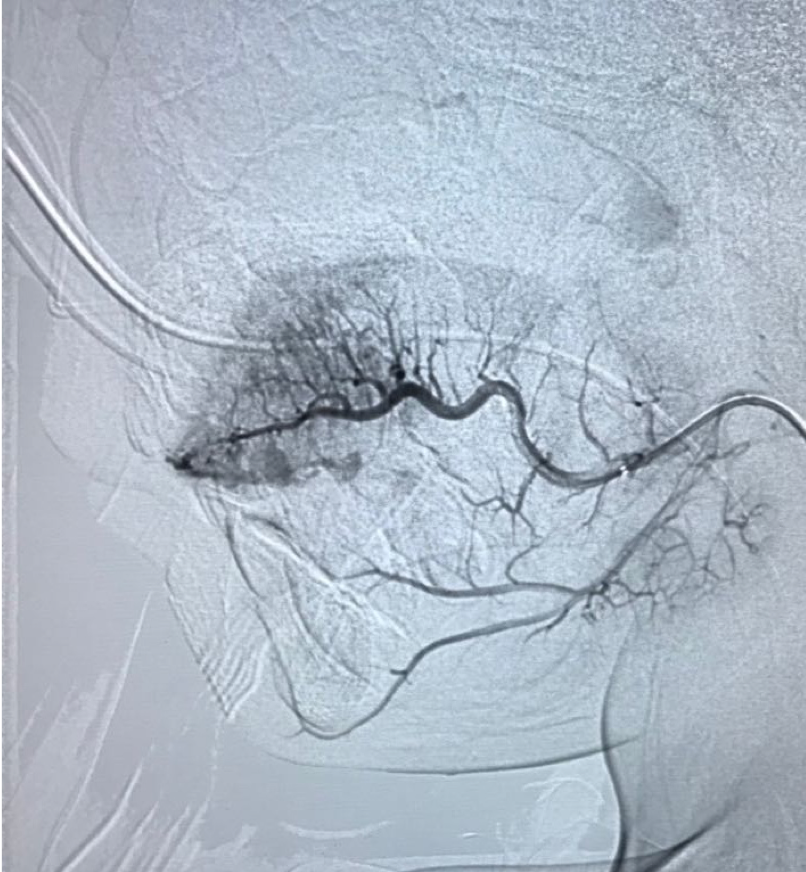

Basics and newer interventions with hands-on workshop